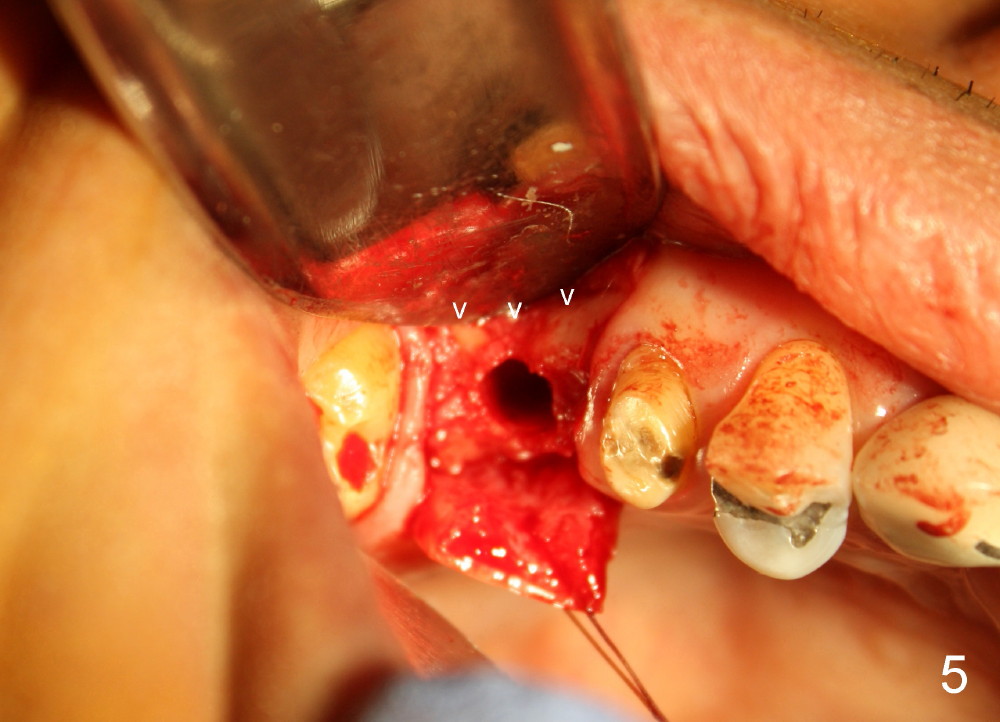

The bone density (Fig.1 white *) at the edentulous area (#3) is lower than that at the dentulous one (black *, 50 year-old man). The buccal plate is also atrophic and concave (Fig.2,3 arrowheads). A series of bone expanders are used to form osteotomy (following 1.6 mm pilot drill) at the depth of 14 mm (Fig.3 E 3.0 mm in diameter). When the last expander (4.3 mm) is removed from the osteotomy, the buccal plate appears to have been moved buccally (Fig.5 arrowheads). A 5.3x14 mm submerged implant (Fig.6 I) is placed with insertion torque >35 Ncm. The buccal plate seems to improve following placement of an 8.2 mm healing abutment and suturing (Fig.7). No bone graft is used. The buccal plate remains normal 12 days postop (Fig.8). It is slightly concave 3 months postop (Fig.9) with minimal bone resorption at the crest (Fig.10 (H: healing abutment),11 (A: cemented abutment). Nine months post cementation (12 months postop), bone resorption at the crest remains minimal (Fig.12) while the buccal plate (Fig.13 *) at #3 remains strong. Bone loss appears not to get worse 22 months post cementation (Fig.14). Soft and hard tissues remain healthy around the implant crown 3 years (Fig.15) and 3.5 years (Fig.16,17) post cementation.